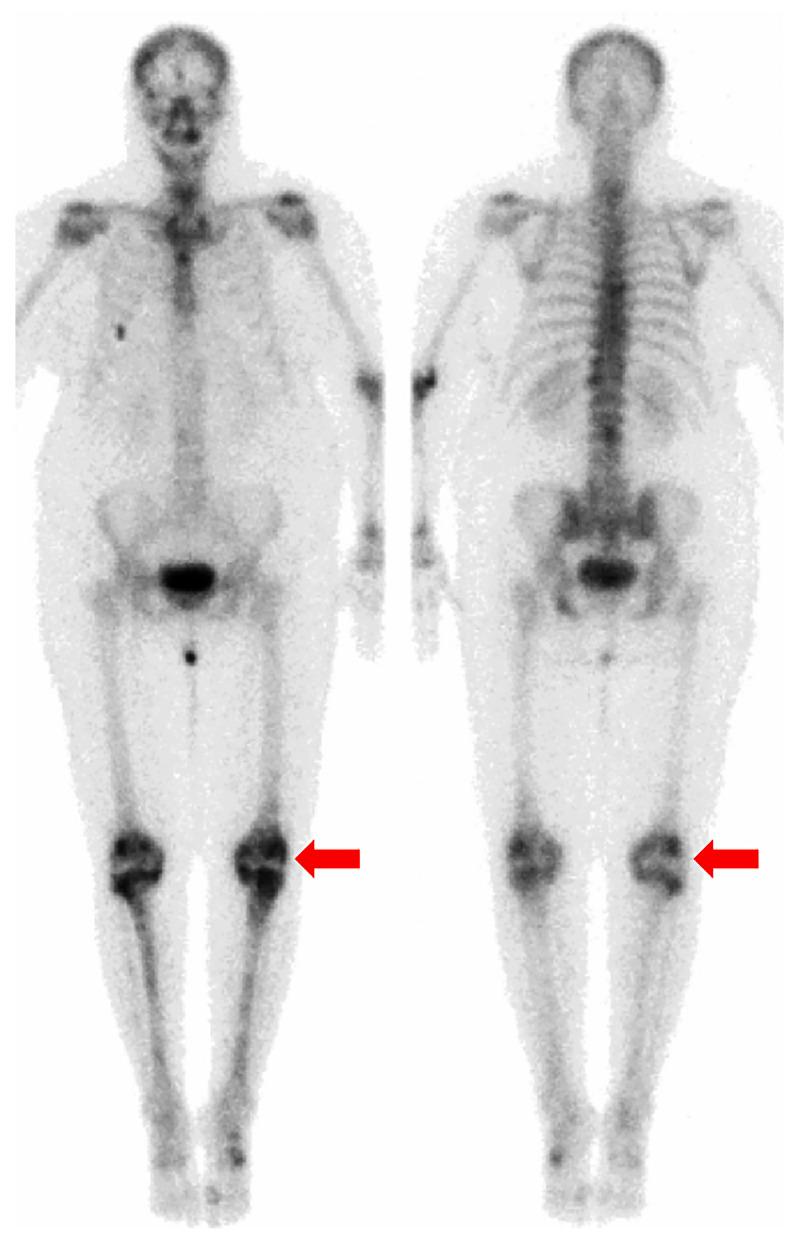

BACKGROUND Erdheim-Chester disease (ECD) is a rare neoplasm of histiocytes that is characterized by prominent involvement of the long bones. Approximately 1500 cases have been reported since the disease was first described in 1930. The imaging appearance of ECD can be highly variable given the numerous systems it can affect. In this case report we discuss a patient whose ECD was occult on multiple imaging modalities. CASE REPORT We report the case of a 60-year-old woman who presented with sub-acute left knee and calf pain that led to an MRI. She was found to have innumerable marrow-replacing lesions in the axial and appendicular skeleton visualized on the initial MRI, as well as on an ¹⁸F-FDG PET/CT scan. The patient did not have extraosseous abnormal uptake on the PET/CT. Subsequently, a lesion from the left iliac bone was histologically confirmed as ECD on the basis of positive staining for CD68 and CD163 and negative staining for CD1a. Osseous lesions in ECD have a distinct imaging appearance and are typically detected by radiography and bone scintigraphy, among other modalities; however, the lesions in this case were unexpectedly absent from those studies. CONCLUSIONS If there is a high degree of suspicion for ECD, 18F-FDG PET/CT and/or MRI may be necessary for adequate visualization of bone lesions, given that those lesions can have an infiltrative nature that may be difficult to image with other anatomic imaging modalities. Use of 18F-FDG PET/CT and/or MRI may also lead to adequate guidance of confirmatory biopsy.

我们报告了一位 60 岁女性的病例,她因亚急性左膝和小腿疼痛就诊,导致 MRI 检查。最初的 MRI 以及¹⁸F-FDG PET/CT 扫描显示,她的轴骨和附肢骨骼中存在无数骨髓替代病变。PET/CT 上患者没有骨外异常摄取。随后,根据 CD68 和 CD163 阳性染色以及 CD1a 阴性染色,从左髂骨病变活检组织学证实为 ECD。ECD 的骨病变具有独特的影像学表现,通常通过 X 线摄影和骨闪烁显像等其他方式检测到;然而,该病例中的这些病变却出乎意料地没有出现在这些研究中。